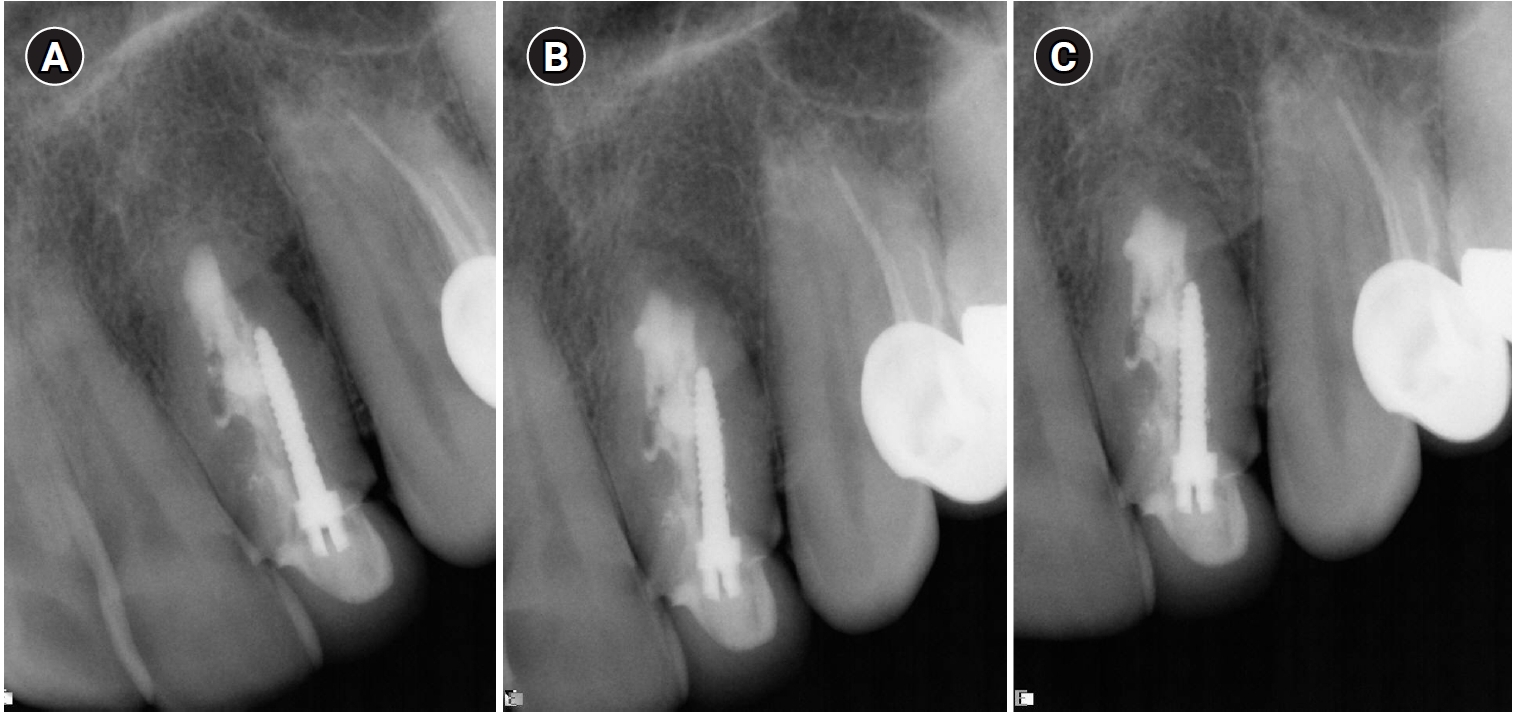

In 2011, 9 years later, the patient came back with a complaint of sensitivity in the area and purulent exudate. Clinically, the tooth was sensitive to percussion and palpation in the periapical area with signs of a sinus tract in the buccal apical area. A diagnosis of chronic apical abscess was made. A second endodontic surgery used the same technique as the previous treatment, taking care to minimize the apical resection in order not to compromise the crown-root ratio. Two years following the second surgery, the tooth was asymptomatic and completely healed radiographically (Figure 3).

Endodontic reoperation on tooth #22. (A) Preoperative radiograph in 2011. (B) Postoperative radiograph in 2011 showing minimal apical resection. (C) Two-year follow-up radiograph in 2012 showing complete healing with normal periodontal ligament space.

Figure 3. Endodontic reoperation on tooth #22. (A) Preoperative radiograph in 2011. (B) Postoperative radiograph in 2011 showing minimal apical resection. (C) Two-year follow-up radiograph in 2012 showing complete healing with normal periodontal ligament space.